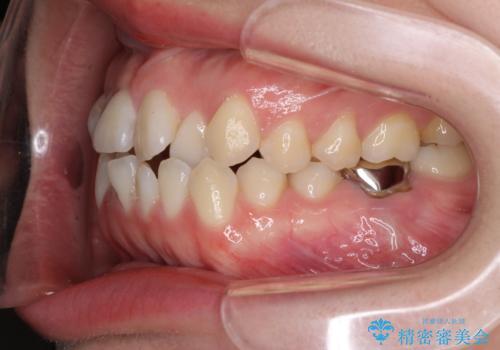

奥の銀歯も気になっていたため、矯正治療後にセラミッククラウンにて補綴することとしました。

セラミック治療の注意事項(リスク・副作用など)

- 天然歯を削ります

- 硬い素材は天然歯を傷つけてしまう場合があります

- かみ合わせや歯ぎしりが強すぎる方はセラミックが割れてしまう可能性があります

- 自費診療(保険適用外治療)となります